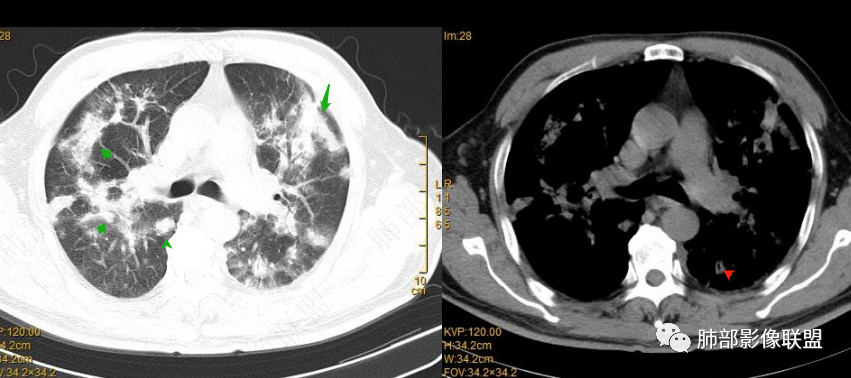

1、部分沿支气管血管束分布,内部支气管通畅,稍扩张。

2、部分外带(距离胸膜下有间隙),与胸膜平行

部分环形融合

首先病灶是距离胸膜有间隙为主,其次是侧向融合,导致长轴与胸膜平行

距离胸膜的位置——提示小叶核心病灶

侧向融合

提示病灶位于小叶核心,逐步增大,到了一定大小之后相互连接,也就是侧向融合

还没有融合的

已经融合的

相对而言:已经融合的,边缘平直、光滑一些,周围纤维化明显一些,没融合的边缘模糊一些,周围GGO多一些;提示融合的病灶更早,已经开始有纤维化改变特点;而没融合的属于后发一些的病灶,纤维成分还不够

提示融合:除了有病灶增大的原因,与纤维化也很大关系

至于这种反晕征状:我认为是外周一层的小叶核心病灶与偏内侧的小叶核心病灶的融合,不是大片状病灶周围的修复所指。

2022.2.17CT显示两肺中内带多发结节影、斑片影、条索影,部分病灶侧向融合与胸膜平行。部分病灶沿着支气管血管束分布、其内支气管稍扩张。部分病灶呈反晕征。大部分病灶边界显示清晰,部分病灶周围可见边界不清的GGO。2022.4.12CT显示两肺中内带多发结节影、条索状、条带状高密度影,边界收缩平直凹陷,大部分病灶沿着支气管血管束分布,亦有位于胸膜下侧向融合与胸膜平行的病灶。总体与第一次CT对比两肺病灶明显吸收。